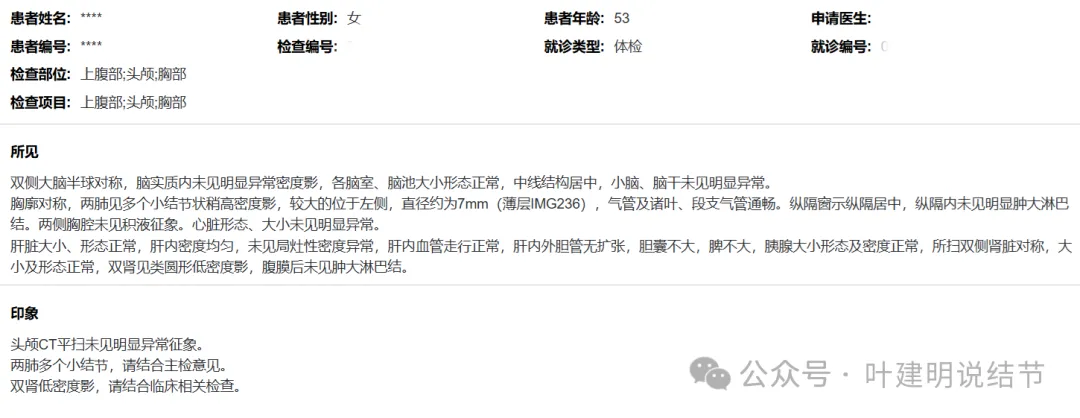

9月体检时是说多个小结节,较大的直径7毫米,在236层面。

上图就是236层面,报告说的结节主要的是指左下这处实性的。